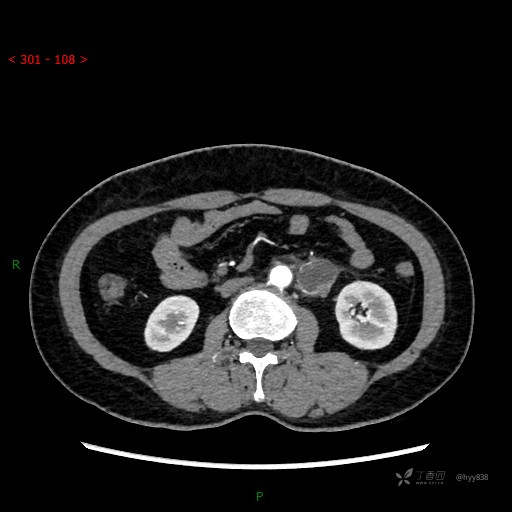

增强动脉期

静脉期

CT平扫是外院的,因图像质量原因,不方便上传!